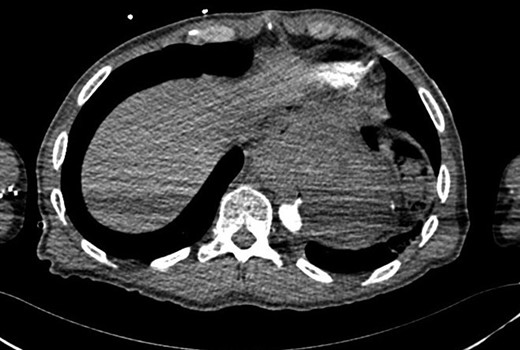

The purpose of this case report is to describe the clinical course of a 57-year-old male who presented with acute onset of massive haematemesis and hypovolaemic shock. His medical history was remarkable for a trans-hiatal oesophagectomy and gastric pull-up for adenocarcinoma 15 years prior. After initial fluid resuscitated, oesophago-gastro-duodenoscopy (OGD) was performed which was complicated by cardiac arrest. He was intubated and fluid resuscitated until haemodynamically stable. Computed tomography aortography (CTA) demonstrated an aorto-oesophageal fistula (Fig. 1). A rapid decision was made to proceed with a TEVAR limited to that segment of aorta using Cook Zenith Alpha 24/105 stent graft. The procedure was successful. The patient was later offered definitive procedure, which he refused. Follow-up OGD after 4 weeks revealed a gastric ulcer, with no abnormal cells on histology, for which he was placed on high dose proton-pump inhibitor.

CT aortogram showing the extravasation of contrast into the stomach.